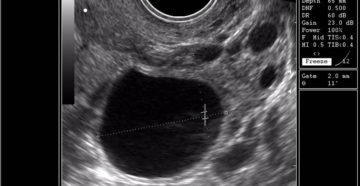

Фолликулометрия как метод определения овуляции — блог Моя БэТэшка В организме женщины под влиянием гормонов…